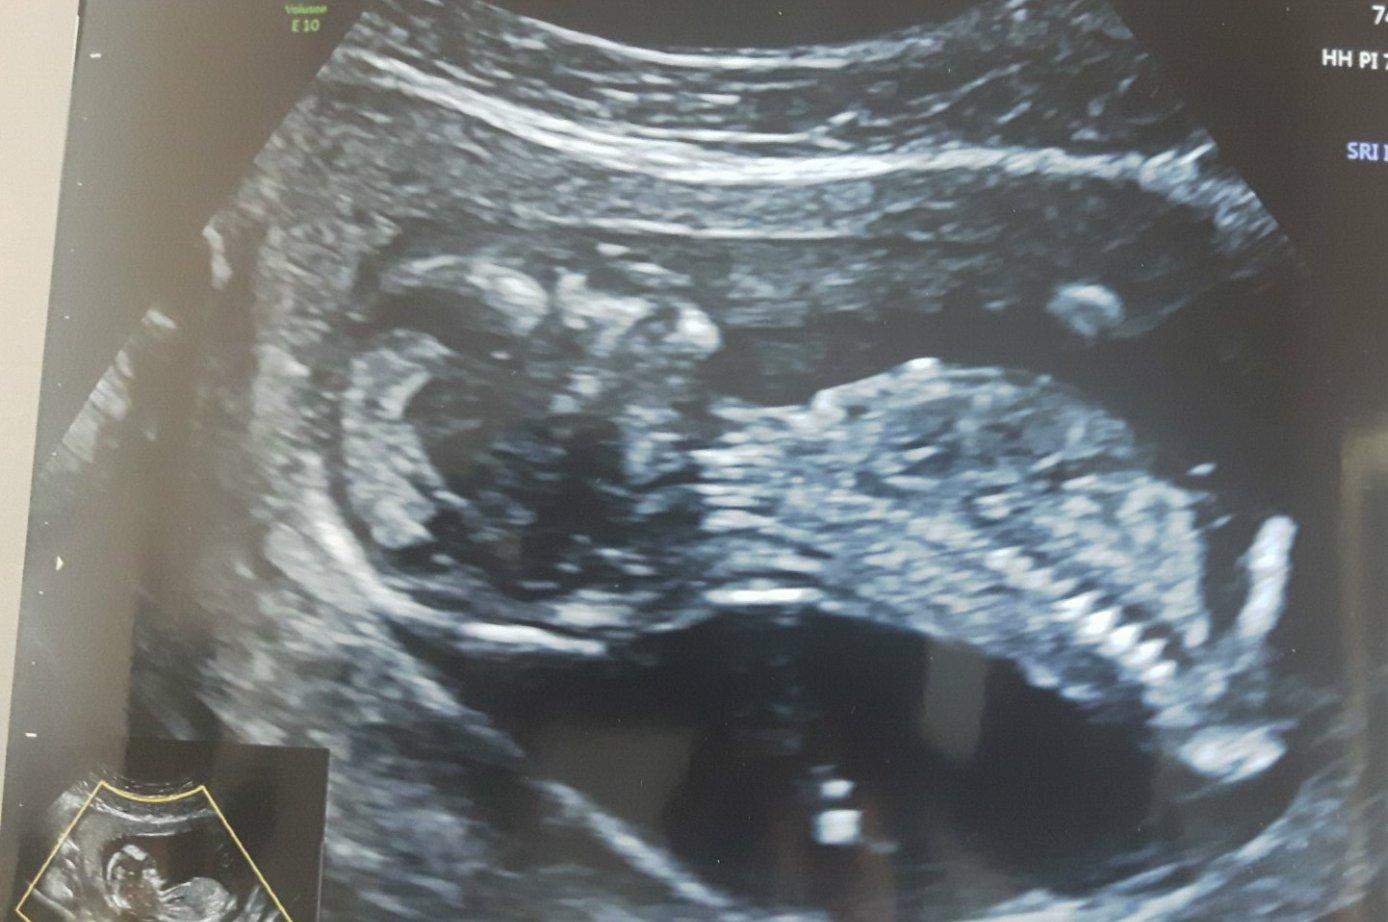

Druhé foto v komentáři 😉

Ahoj, tipuji horni kluk a druhe holcicka? 😀

Ahoj , tipuju to same, horni je kluk, druhy obrazek holka??

tipuju dva chlapáky

Myslím, že dole je holčička, ale první netuším.

Holčička a kluk?